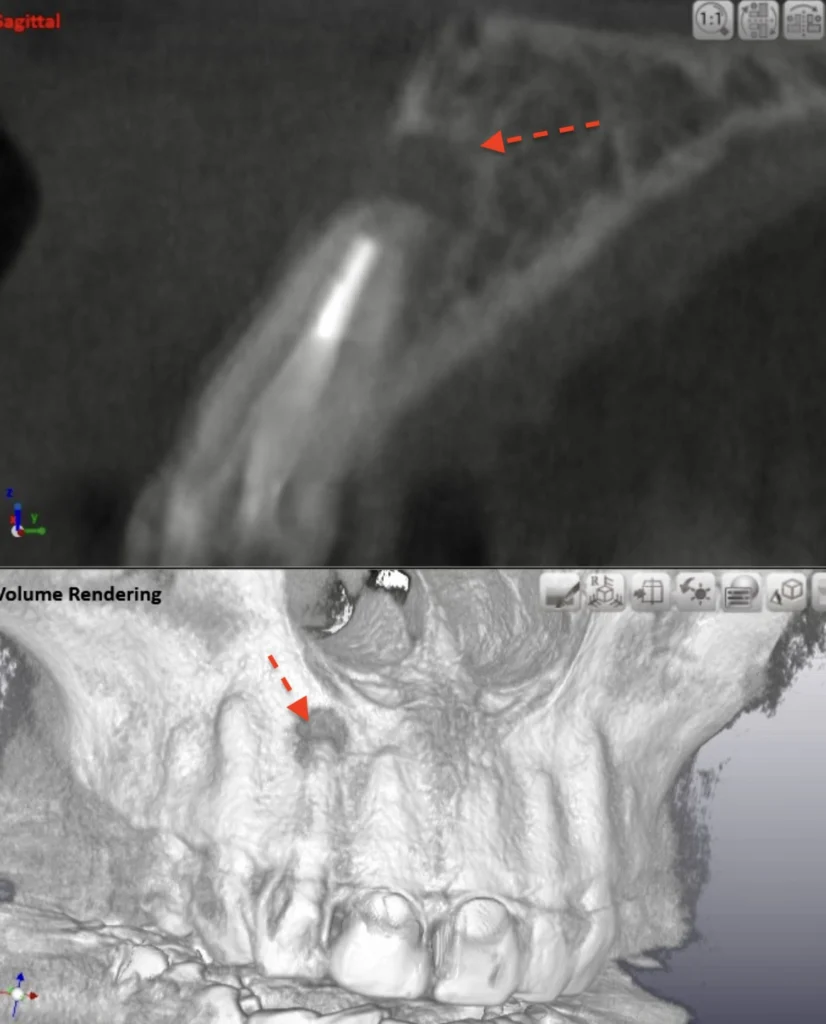

CT画像

唇側の顎骨が溶けて穴が空いています

精密根管治療(自費根管治療)治療開始

精密根管治療(自費根管治療)、治療回数2回、治療期間約2週間、治療費6万8千円+4,500円X1回

歯根端切除術逆根管充填処置(外科的根管治療)

歯肉への切開が必要です、ウミの袋も取り出します